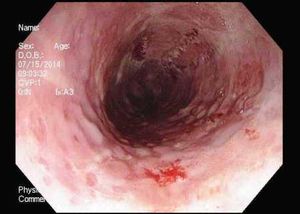

These endoscopic findings help explain worsening dysphagia in a 32-year-old man. Esophageal biopsies prove positive for eosinophilia. How would you proceed?

A 28-year-old man reports pain on swallowing of a week's duration. He is otherwise in good health. Upper endoscopy and tissue biopsy reveal the cause. What do you see?

The most frequently encountered cause of infection of the esophagus is Candida. Among viral causes HSV is the most common, followed by CMV.